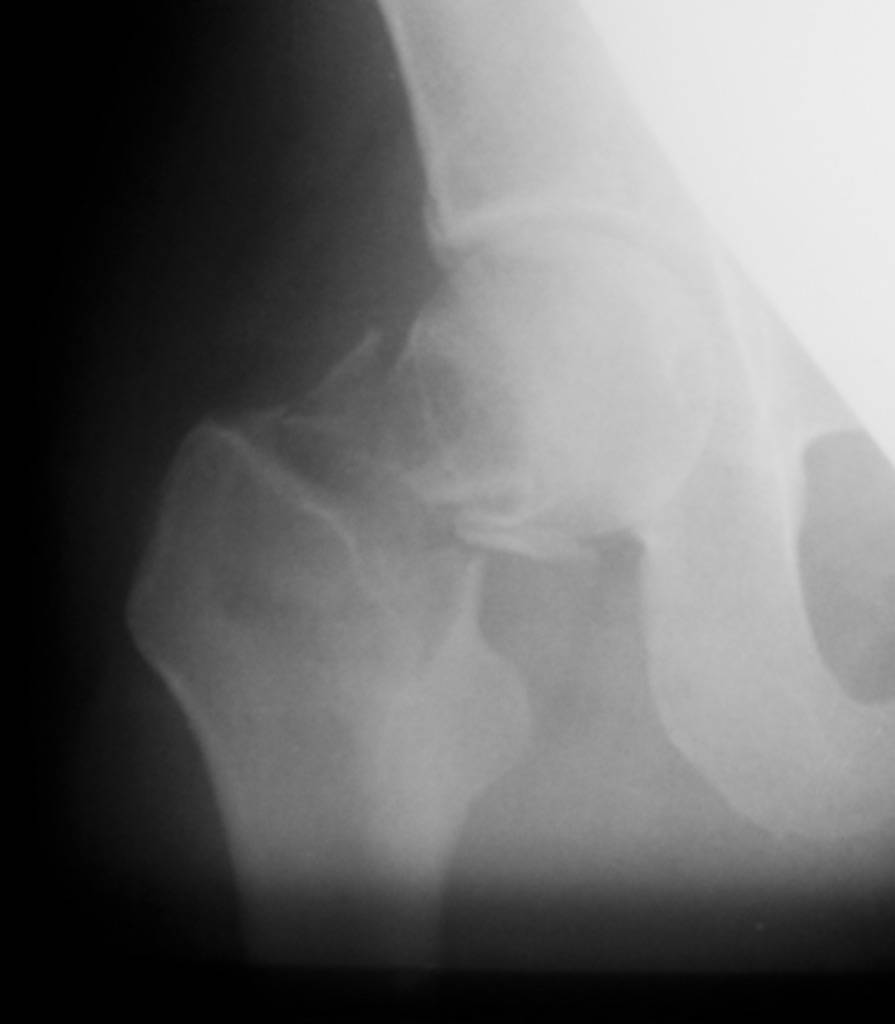

Приношу извинения, думал, что на прилагающейся рентгенограмме видно, что перелом произошел на месте обширной кисты, занимающей шейку и вертельную область. По характеру перелом многооскольчатый, дуга Адамса также представлена в виде осколков.

Если нет подозрений на первичную злокачественую опухоль, тогда опять остеосинтез, но конструкцией с угловой стабильностью, т.е. либо гамма/PFN (я бы выбрал), либо DHS. Без пластики. Вероятно, КТ могла

бы уточнить протяженность. Но головка выглядит хорошо, есть за что зацепиться.

"Поправил" рентгенограмму. Так не лучше?